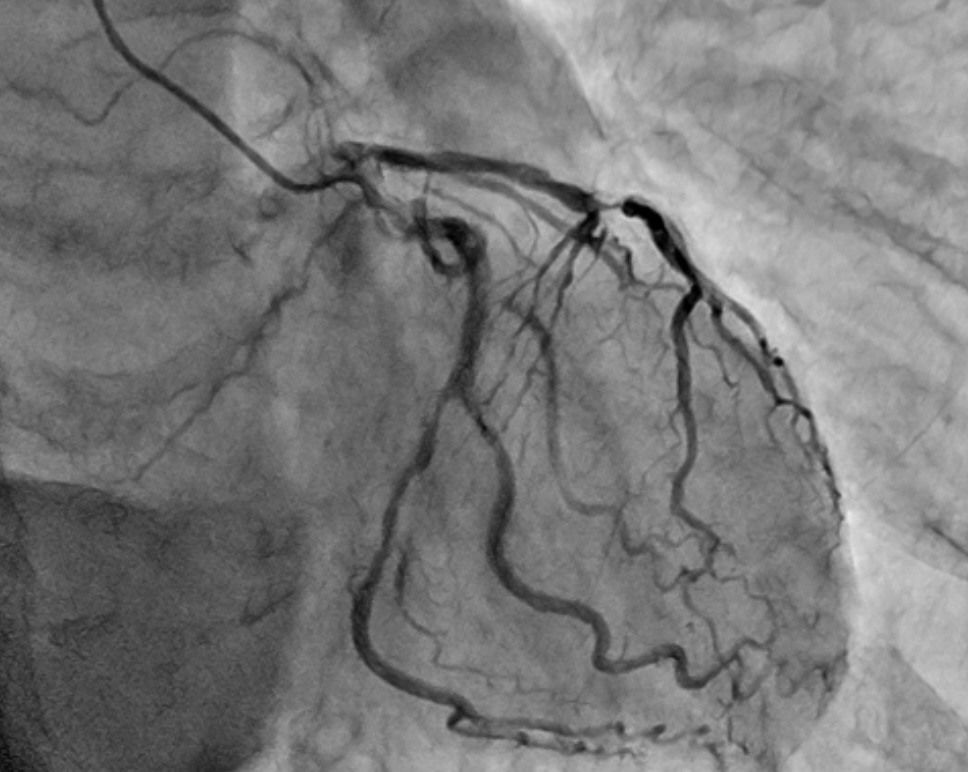

Coronary angiography revealed tandem lesions in the left anterior descending artery and a severe stenosis in the circumflex artery. The proximal left anterior descending artery was a severe bifurcation lesion (Fig 2 and 3).